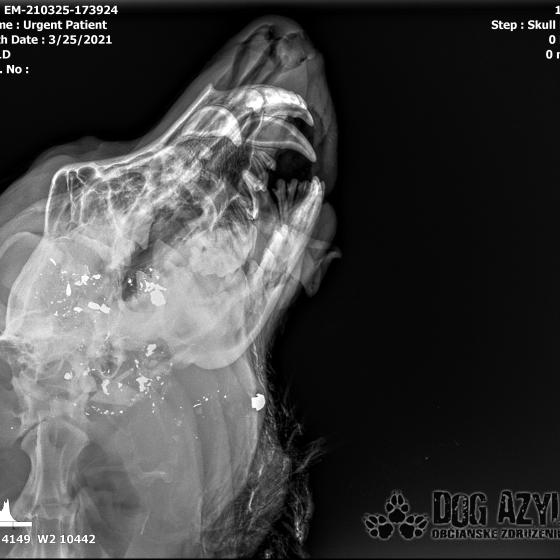

Ona ležala na ľavo, on na pravo od zavesenej šunky, ktorá mala zrejme slúžiť ako návnada, aby sa terče nehýbali.. Uprostred ničoho, bez svedkov, bez dôkazov... Pár kvapiek krvi na ceste.. Ona to schytala jedinou ranou do srdca.. On má roztrieštenú sánku, schytal to do hlavy..

/Strašne to chcem dopísať tak, aby to bolo čitateľné a pochopiteľné, ale celá sa klepem od zlosti a nevidím cez slzy.../ Lebo Ona už meno nikdy nebude mať.. On dostal meno Baris a bojuje o život!!! Má dolámanú sánku a je v šoku!!! Dostal prvú pomoc, analgetiká a priorita bola znížiť jeho teplotu z 41,4°C!!!

Ústami nevie pohnúť, jazyk si nevie ovládať a tak sa sám nedokáže schladiť ani napiť. Podľa RTG sú srdiečko a pľúca v poriadku, ale vôbec nemá vyhraté!!! Niekto chcel Barisa zlikvidovať, ale my za neho budeme bojovať do posledného dychu!!! Zajtra bude prevezený na veterinárnu kliniku Sibra centrum, kde ho čaká team špecialistov z oblasti chirurgie, neurológie a ortopédie. Ak je čo i len najmenšia nádej, že Baris bude môcť žiť, tak BARIS BUDE ŽIŤ!!!